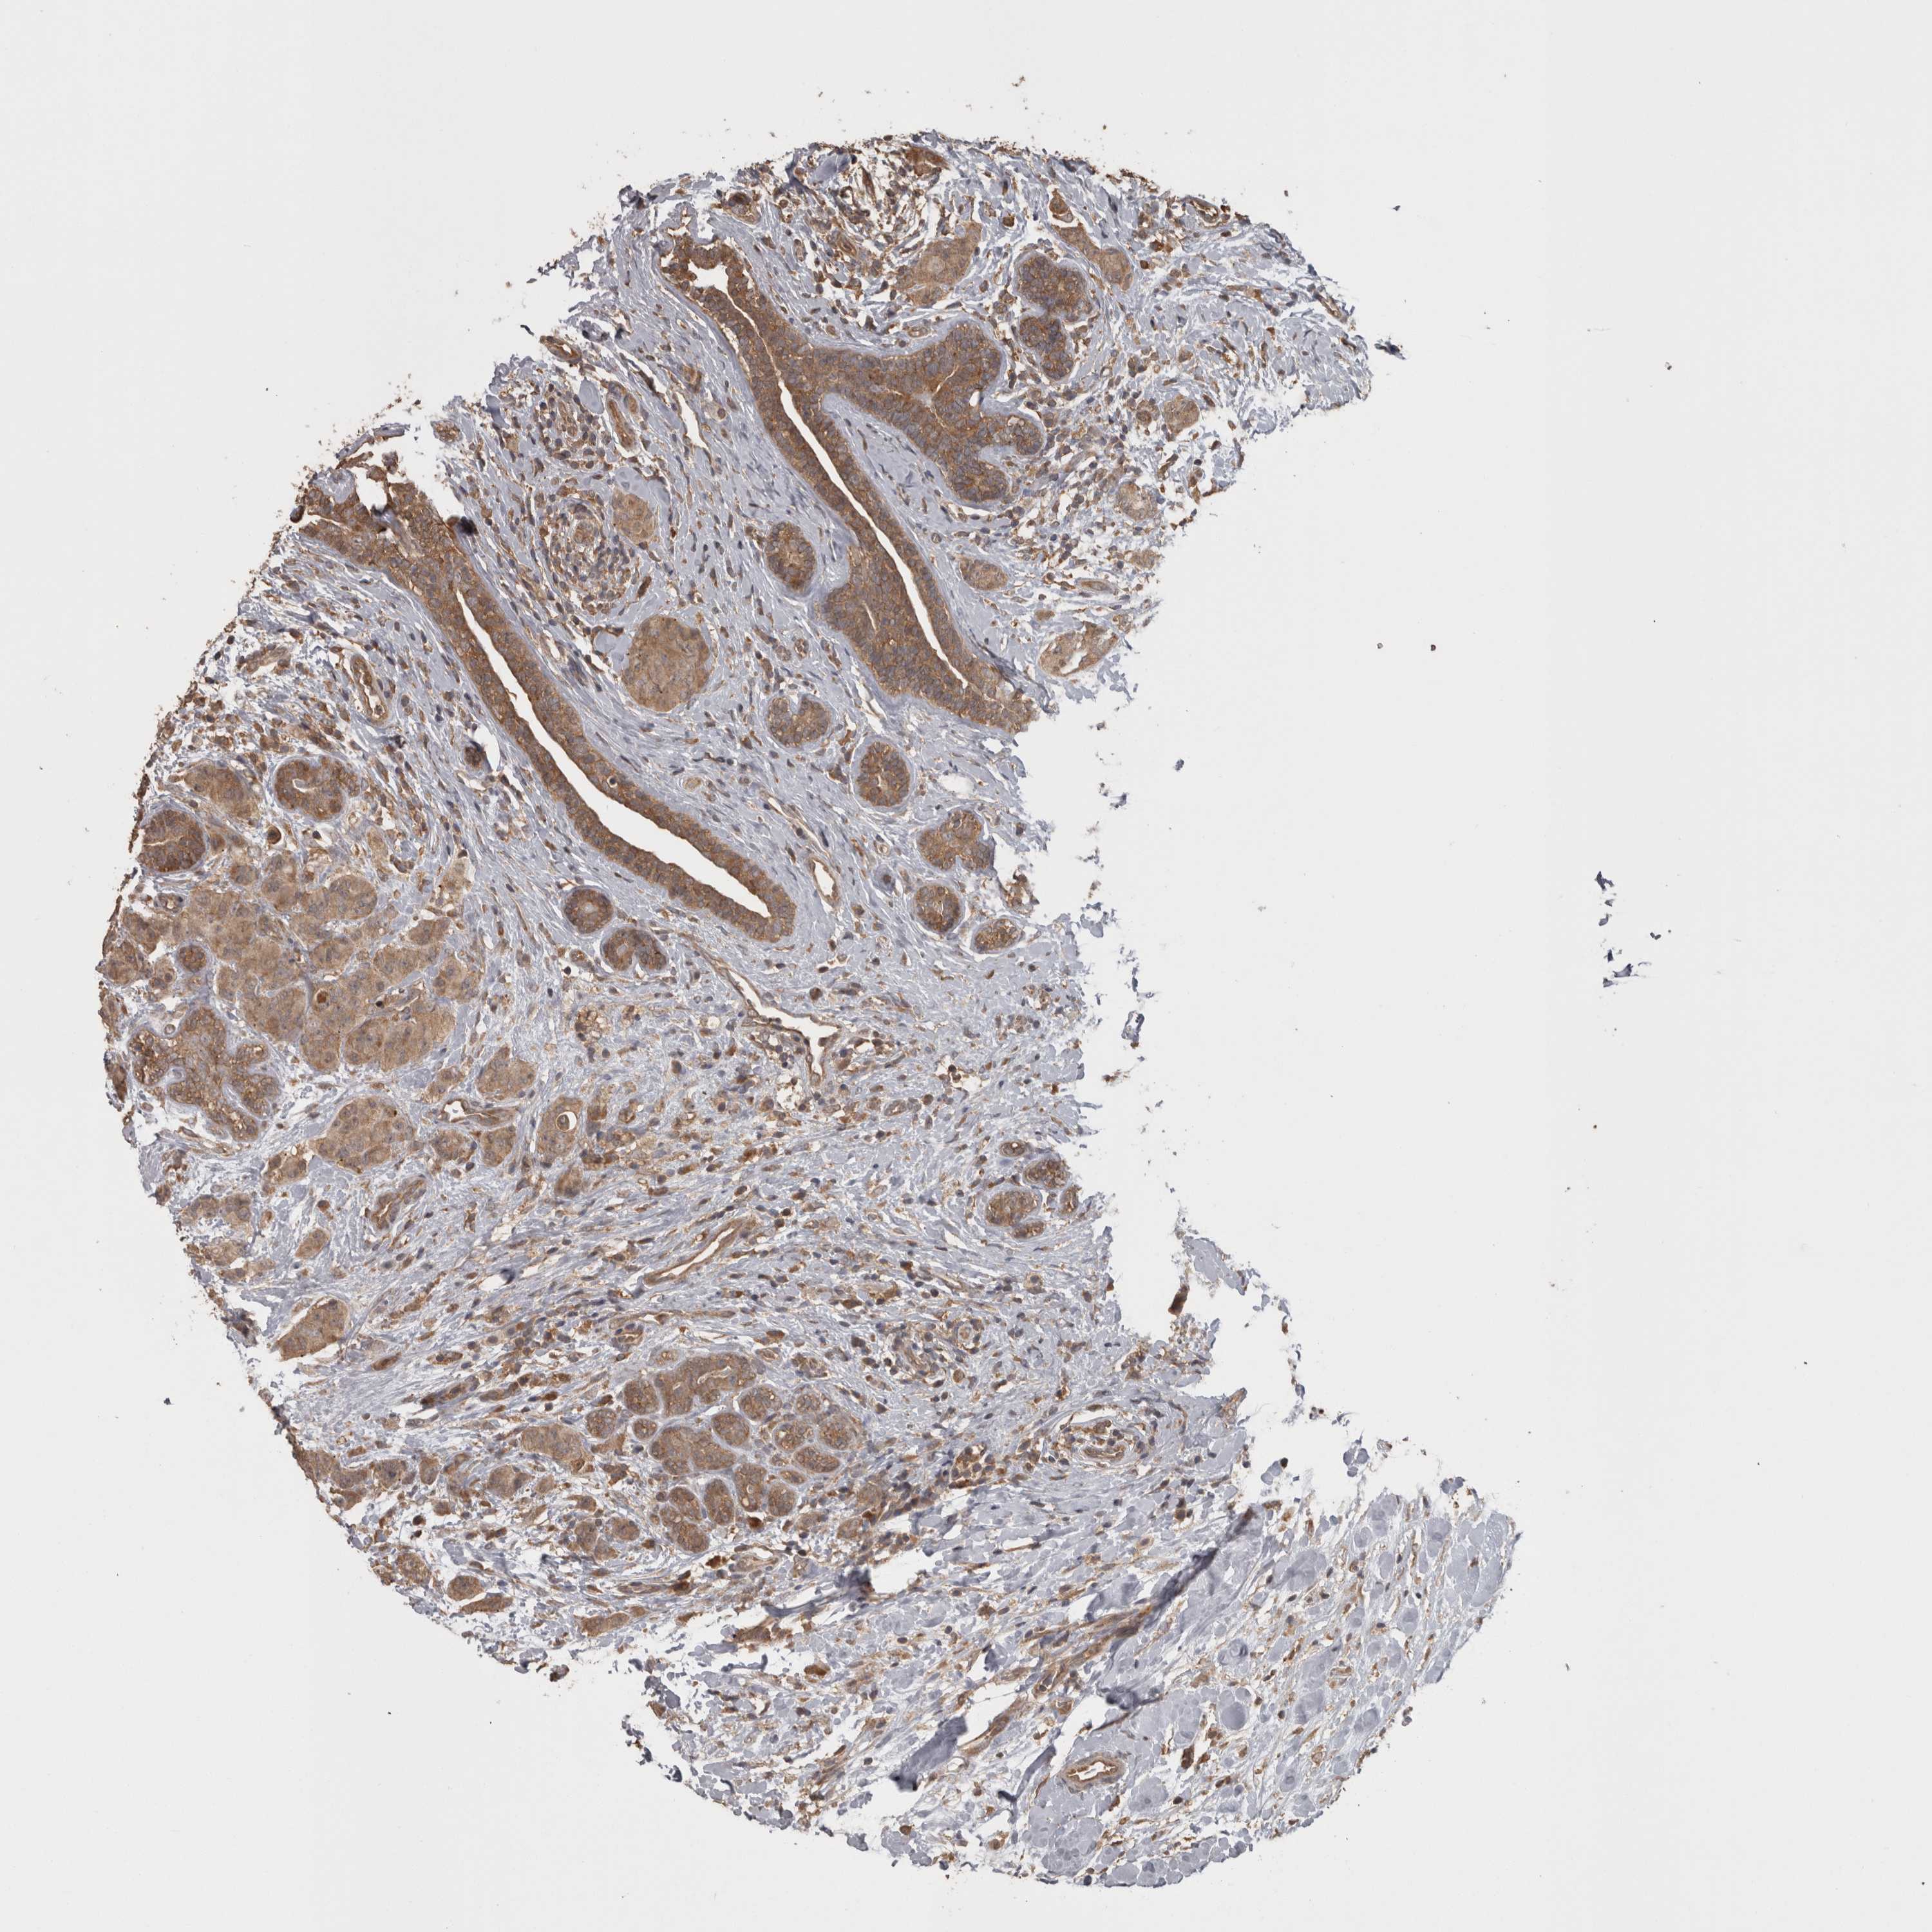

CANCER BREAST CANCER Show tissue menu

BRCA TCGA BRCA VALIDATION PROTEIN EXPRESSION

ANTIBODIES

AND

VALIDATION